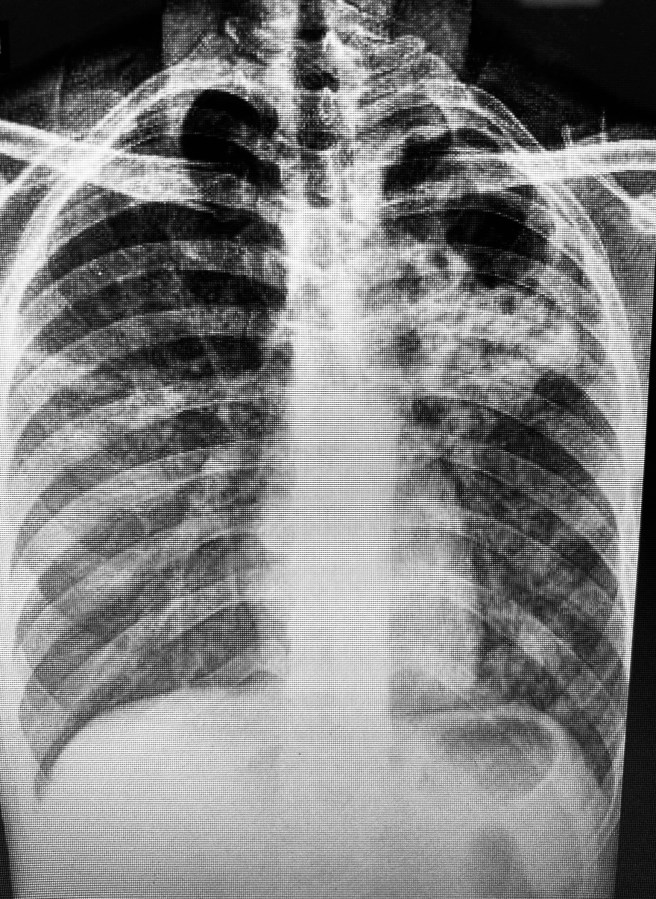

Existem radiografias compatíveis, sugestivas e até típicas, e existe essa, o protótipo da imagem de tuberculose em uma radiografia de pulmão. Cortesia do Serviço de Infectologia do Hospital Regional de Presidente Prudente.